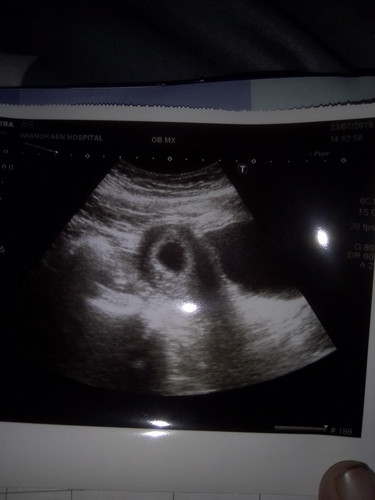

กลัวท้องลม

วันนี้ไปอัลตร้าซาวด์มาหมอบอกว่าพบแต่ถุงยังไม่พบเด็กเดี๋ยวอีก1เดือนมาอัลตร้าซาวด์อีกครั้งกลัวจะเป็นท้องลมค่ะทำไงดีค่ะ

ตั้งครรภ์อ่อนๆส่วนใหญ่จะยังไม่เห็นถุงตั้งครรภ์จ้ะแม่ รอหมอนัดซาวอีกทีน้า